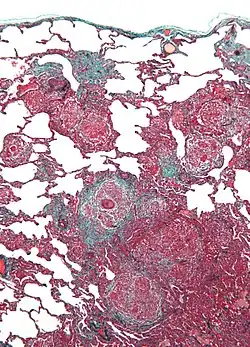

| Micrograph of hypersensitivity pneumonitis, the histologic correlate of bird fancier's lung. Lung biopsy. Trichrome stain. | |

Bird fancier's lung (BFL), also known as bird breeder's lung or pigeon lung, is a type of hypersensitivity pneumonitis. It can cause shortness of breath, fever, dry cough, chest pain, anorexia and weight loss, fatigue, and progressive pulmonary fibrosis (the most serious complication). It is triggered by exposure to avian proteins present in the dry dust of droppings or feathers of a variety of birds. The lungs become inflamed, with granuloma formation. It mostly affects people who work with birds or own many birds.

Lung biopsy usually reveals non-necrotizing granulomatous inflammation.[7] It also shows "foamy" macrophages and crystals of oxalic acid.[3] Hyperplasia tends to occur in type 1 pneumocytes and not in type 2 pneumocytes.[3]